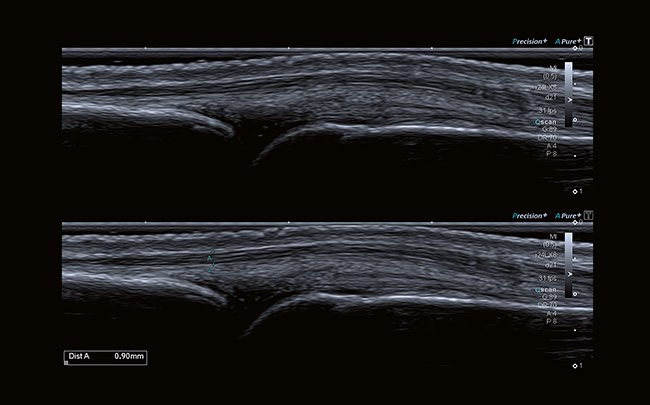

Компоненты ApliPure ™ + обеспечивают повышенную контрастность изображения и уменьшают спекл-шум для улучшения визуализации.

Дифференциальные тканевые гармоники обеспечивают гармоничные изображения непревзойденного пространсвтенного разрешения, а также значительно улучшенное проникновение

Технология Precision + позволяет получать однородные изображения, четкие углы и контуры.